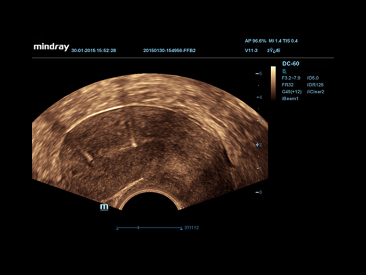

PSH??(Phase Shift Harmonic Imaging)

Purified Harmonic Imaging for better contrast resolution providing clearer images with excellent resolution and less noise.

iBeam?

Permits use of multiple scanned angles to form a single image, resulting in enhanced contrast resolution and improved visualization.

iClear?

Gain improved image quality based on auto structure detection

?┬Ę Sharper & Continuous Edges

?┬Ę Smooth Uniform Tissues

?┬Ę Cleaner ŌĆśno echo areasŌĆÖ